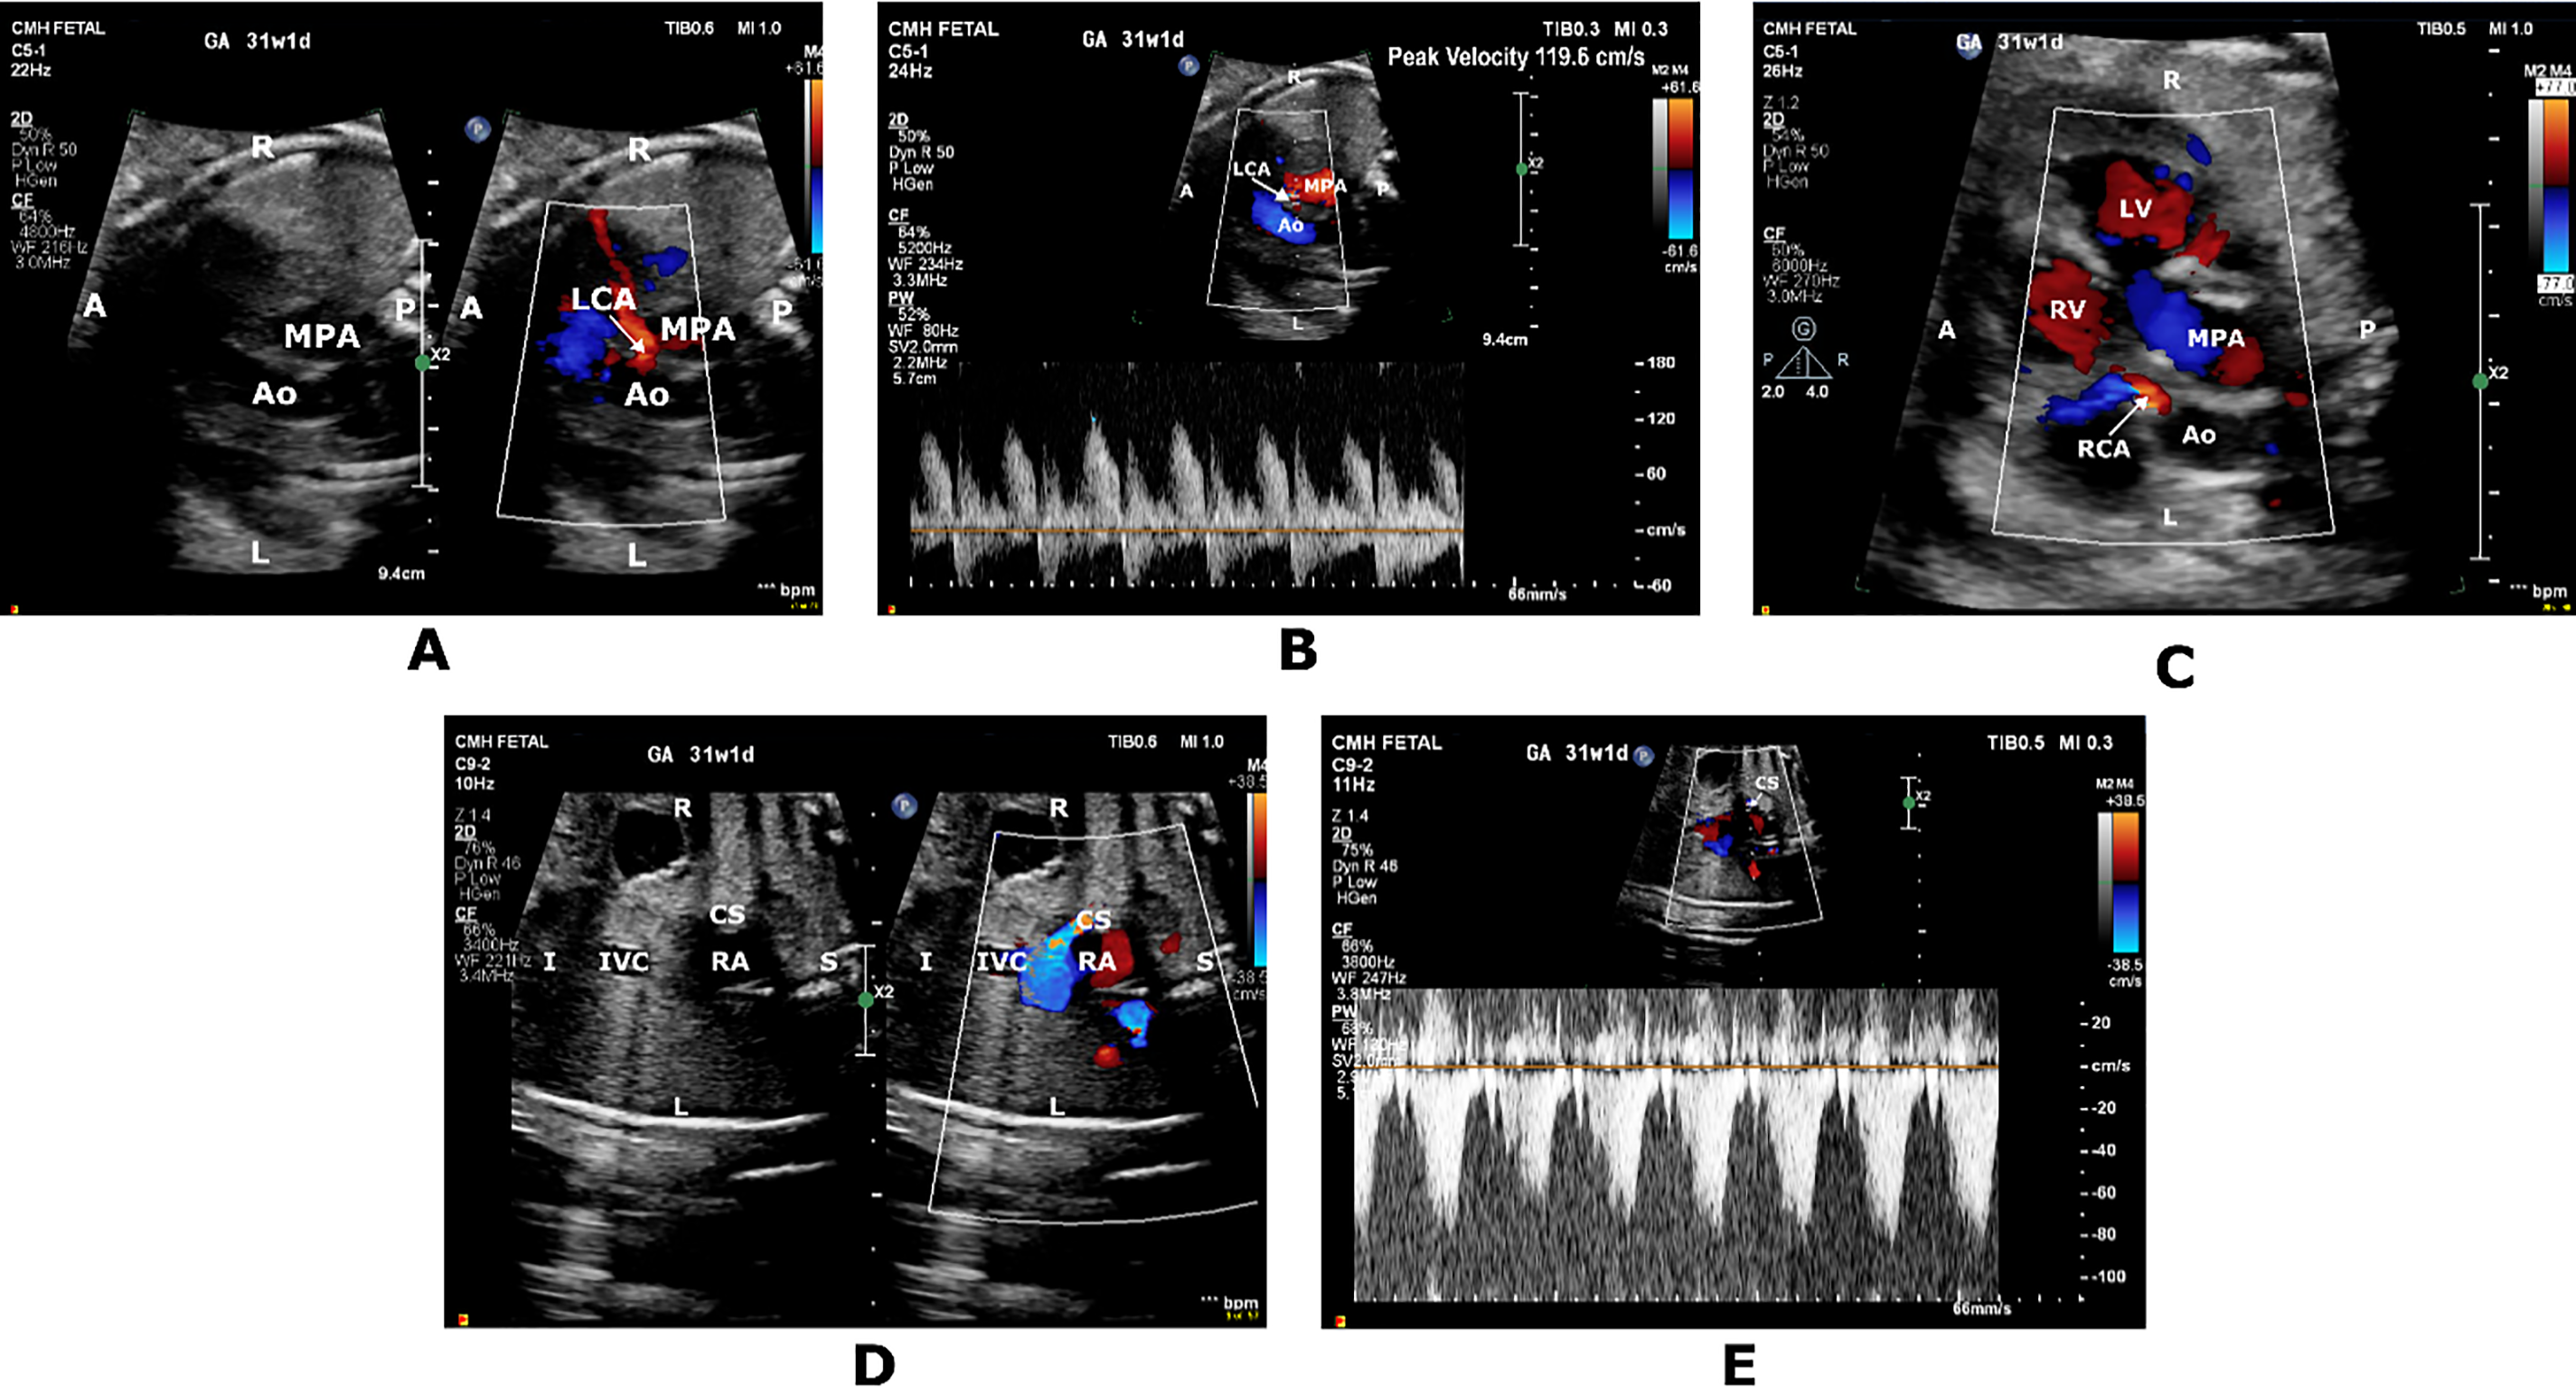

Fetal referral at 31 weeks’ gestational age (GA) for suspected complex CHD indicated the need for a fetal echocardiogram (FE) that demonstrated situs inversus totalis, dextrocardia and transposition of the great arteries (TGA) with atrial situs inversus, l-looped ventricles and l-malposed great vessels. There was mild cardiomegaly (right atrial and ventricular dilation), biphasic inflow Dopplers, and qualitatively normal biventricular systolic function. A CAF from the rightward aortic sinus was suspected to be heading towards the left ventricular free wall and terminating in the coronary sinus (CS) (Fig. 1). No flow reversal was seen in the ascending aorta. Prominent flow was also noted in the right CA. Umbilical artery (UA) pulsed wave Doppler (PWD) showed a pulsatility index (PI) of 0.61 (<5th percentile), Middle cerebral artery (MCA) PWD showed a PI of 0.65 (<5th percentile), and cerebroplacental ratio (CPR) of 1.07 (<5th percentile). Umbilical venous (UV) and ductus venosus (DV) Dopplers were normal. A week later, fetal heart rate decelerations prompted an emergent C-section. A female infant weighing 1810 g (64th percentile) with Apgar scores of 7,8 was delivered. Postnatal echocardiogram confirmed the prenatal CHD diagnoses with typical coronary origins for TGA, but no CAF was identified. Biventricular systolic function was normal with left ventricular ejection fraction (LVEF) of 61%. Placental histopathology demonstrated evidence of focal chorangiosis. UA pH and pO2 were 7.27 and 21 mmHg, respectively. A successful arterial switch operation was performed at 7 weeks of age.

Figure 1: Short axis color-compare image (A) and pulsed wave Doppler tracing (B) showing prominent high-velocity diastolic flow originating from the rightward aortic sinus into the left coronary artery (LCA) territory. Short axis color Doppler image (C) showing prominent filling of the right coronary artery (RCA). Coronal color-compare image (D) and PWD tracing (E) showing prominent flow at the coronary sinus (CS) ostium returning to the right atrium (RA). A, anterior; Ao, Aorta; I, inferior; IVC, inferior vena cava; L, left; LV, left ventricle; MPA, main pulmonary artery; P, posterior; R, right; RA; right atrium; RV, Right ventricle; S; superior

In Case 1, we suspected a CAF from left coronary artery (LCA) to the CS. The UA and MCA indices did not corroborate brain sparing given PI values for both parameters were below the 5th percentile. No other markers indicated a fetal hypoxemic state or myocardial dysfunction. Inflow Dopplers were biphasic, and biventricular systolic function was preserved. PWD DV showed no a-wave reversal, and UV Doppler showed no pulsations. However, on follow-up, the fetus clearly demonstrated signs of in utero distress with heart rate decelerations leading to delivery. In retrospect, the finding of prominent CA flow in both coronary territories should have raised the possibility of heart-sparing rather than a CAF. Additionally, we suspect that, in this case, prominent CA flow was an early marker of acute fetal stress preceding the development of extracardiac Doppler abnormalities or cardiac dysfunction.